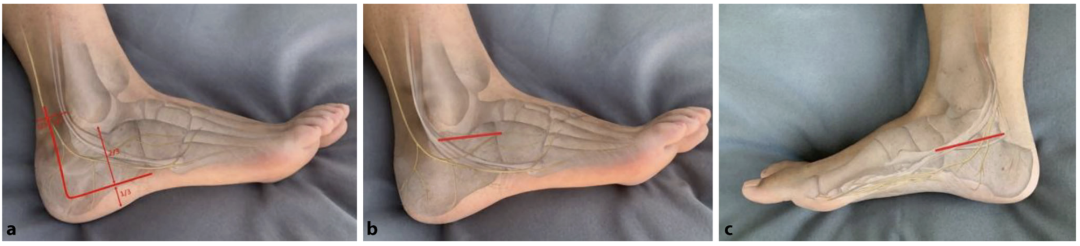

借助经皮置入的带 T 型手柄的斯氏针,采用摇杆技术对跟骨结节骨块进行可控操作,术中可将Böhler角的矫正情况作为复位参考指标。复位后的跟骨结节骨块需用克氏针临时固定于通常较为稳定的内侧载距突骨块(恒定骨块)。亦可采用骨撬进行复位,沿骨折线置入骨撬,沿骨折缝隙轻柔撬拨,精准松解并将跟骨结节复位至内侧壁。

对于移位明显的舌型骨折,跟腱的牵拉会增加关节面解剖复位的难度。此类病例中,可采用Essex-Lopresti手法,将 2 枚粗克氏针置入支撑关节面与跟腱止点的舌型骨块,通过向远侧旋转的摇杆动作直接复位骨块。若上述手法复位失败,可在关节面背侧对舌型骨块行冠状面截骨,先复位关节面,再复位跟骨结节骨块。